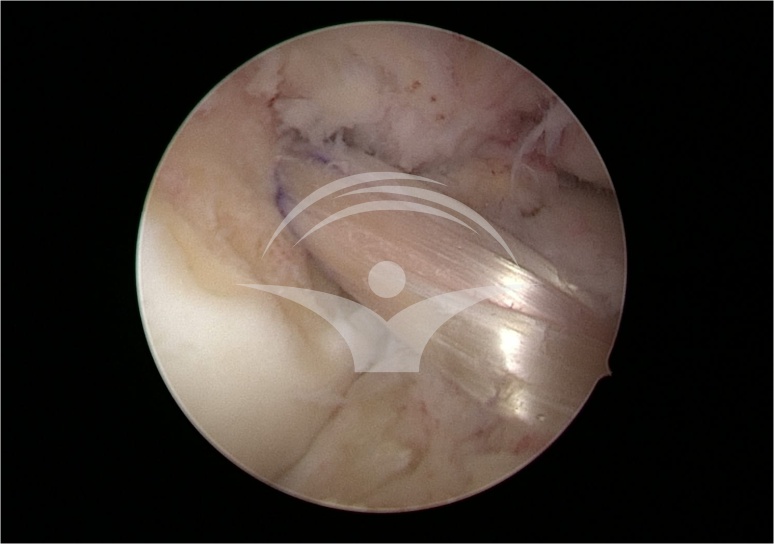

Pentru ca rupturile de ligament incrucisat anterior (LIA) nu se vindeca de la sine, ligamentul trebuie sa fie inlocuit (reconstruit). Reconstructia ligamentara se realizeaza prin tehnici asistate artroscopic.